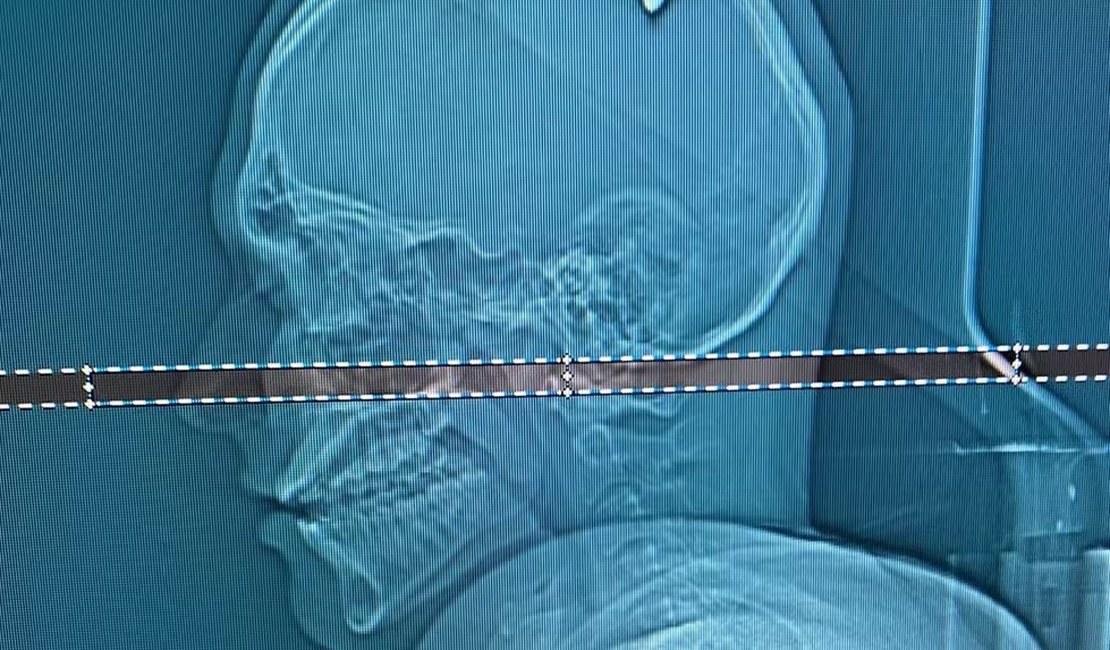

Após exames em um hospital particular de Juiz de Fora, foi identificada a bala, de calibre 9 milímetros, alojada na cabeça dele.